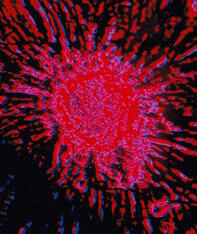

Stephen Cherniske : Faux ! La DHEA est un régulateur cellulaire. Elle induit l'apoptose (la mort cellulaire) dans les cellules malignes ou qui fonctionnent mal5 et contrôle l'hyperplasie (la croissance anormale des cellules) dans les muscles lisses des poumons6. Dans de nombreux modèles animaux, on a montré qu'elle imite les effets bénéfiques anticancer et de régulation cellulaire de la restriction calorique7. |

Stephen Cherniske : Aucune donnée ne le suggère. En fait, toutes les preuves indiquent le contraire. Le Dr Marien Laderoute, un médecin légiste du Bureau canadien des maladies infectieuses, nous rappelle que le cancer est associé à de faibles niveaux de DHEA. Elle et d'autres soulignent que les mutations spécifiques nécessaires à la carcinogenèse peuvent être retrouvées dans une défaillance de l'immunité et de la régulation cellulaire qui se produit comme conséquence de niveaux abaissés de DHEA10. |

Clairement, le cancer ne se développe pas à cause de niveaux élevés de DHEA. Si c'était le cas, des jeunes auraient un cancer alors qu'il est extrêmement rare chez les jeunes. Une immunité déclinante doit être un facteur, mais nous ne voyons pas non plus l'incidence des cancers augmenter chez de jeunes patients suivant un traitement immunodépresseur (par exemple les bénéficiaires d'une transplantation d'organe). L'incidence du cancer est liée à différents aspects du vieillissement incluant des troubles de l'apoptose, une diminution de la surveillance immunitaire et une réduction du nombre et de l'activité des cellules NK (tueuses naturelles). On a montré que la DHEA améliore ces différents facteurs11. |

La recherche actuelle montre aussi que la DHEA, comme la restriction calorique, réduit la génération d'oxyde nitrique, une autre façon de diminuer le risque de cancer12. Au niveau génétique, l'activité anticancer de la DHEA inclut une diminution des niveaux de gènes mutants p5313. De plus, vieillissement et cancer sont associés à un dérèglement de la production de cytokines donnant une prédominance de l'IL-6 sur l'IL-2. On sait que l'IL-2 a une puissante activité anticancéreuse et des injections d'IL-2 sont actuellement utilisées en Europe à différents stades de cancer. Comme on a montré qu'une DHEA optimisée augmente de façon significative les niveaux d'IL-2 et normalise l'équilibre des cytokines, maintenir des niveaux optima de DHEA semble être une stratégie efficace de prévention du cancer. |

En fait, des études animales ont soutenu cette idée pendant 25 ans et l'administration de DHEA a réduit le risque de cancer du foie, des surrénales, du pancréas, du sein, du poumon, de la thyroïde, du colon, de la peau et des tissus lymphatiques14. |